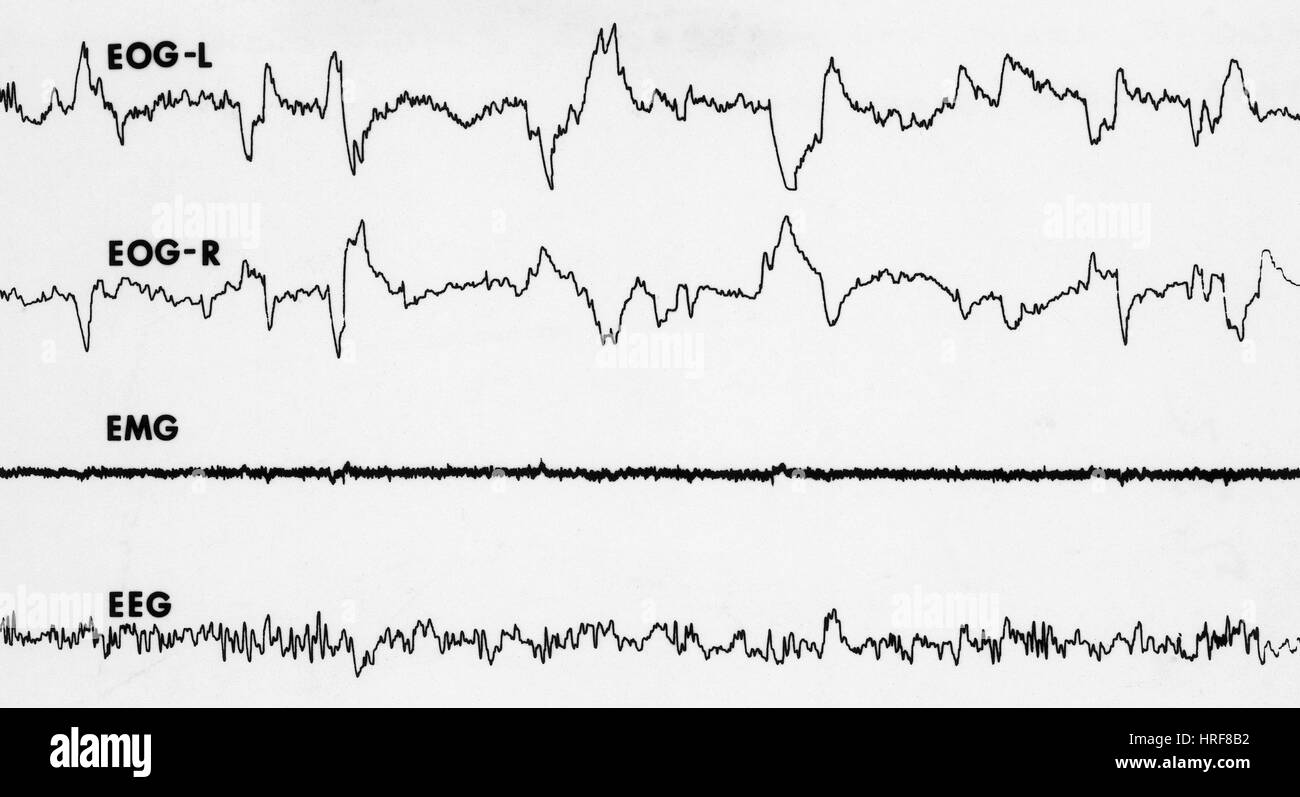

Polygraphic records of EEG, EOG and EMG showing signs of REM sleep Rem Sleep Eeg Pattern but there is more to rem sleep than meets the eye. The electroencephalogram (eeg) reveals a. rem sleep is the third major physiological state of vigilance, beside wakefulness and nrem sleep. Stage iv sleep is defined by slow waves (also called delta waves) at. rem sleep is characterized by lateral eye movements, seen on eeg as opposing. Rem Sleep Eeg Pattern.

Polygraph Tracings of REM Sleep Stock Photo Alamy Rem Sleep Eeg Pattern The electroencephalogram (eeg) reveals a. but there is more to rem sleep than meets the eye. Stage iv sleep is defined by slow waves (also called delta waves) at. rem sleep is the third major physiological state of vigilance, beside wakefulness and nrem sleep. rem sleep is characterized by lateral eye movements, seen on eeg as opposing. Rem Sleep Eeg Pattern.